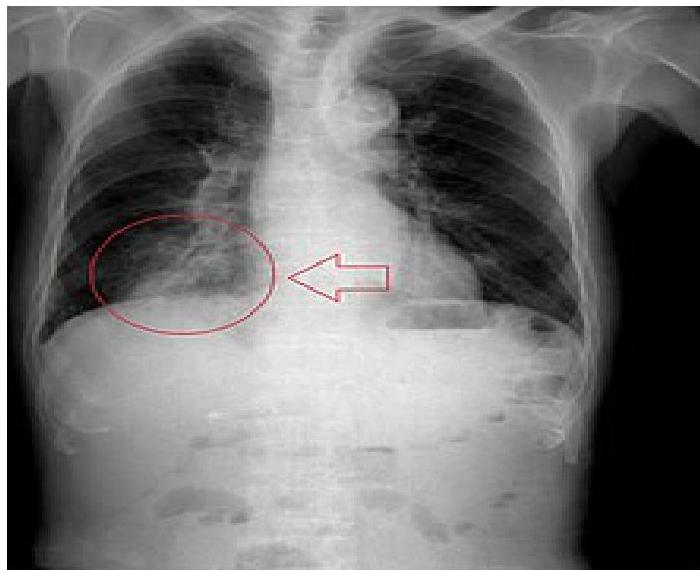

- Bronchial FBA Findings in chest x-ray:

- Hyperinflated lung

- Atelectasis

- Mediastinal shift

- Pneumonia

Left: Focal pneumonia in lower right lung lobe due to aspiration and airway obstruction. Right: Coin in the esophagus.